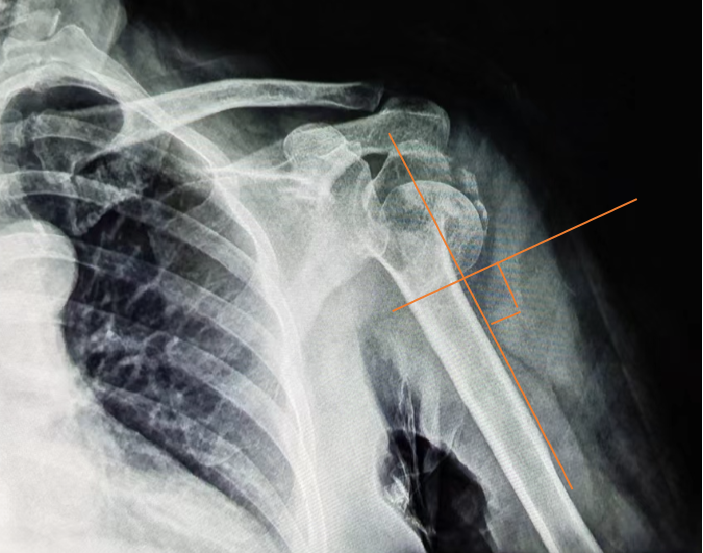

女,64岁,患肱骨近端粉碎性骨折10余天。骨折粉碎程度高,在躯干与肢干交界处的肱骨近端四部分骨折,成角角度约90度。

此时手法整复意义不大,又因家境困难,且患者本人惧怕手术,于是我们开启了医患焦虑的慢慢保守治疗之路,在“错位骨折如何得到最大化纠正”的力学固定上动足了脑筋。

第一部分的力由腋下处的夹板(笔者特别制作)提供的一个向上的力(F1),另一个则是支撑远端骨折的垂直肱骨干向上的力(F2)。

第二部分的力在断端下缘处额外增加一个小树皮,使之有一个向上的托举力(F3)。

第三部分的力通过“胶布墙”制造的牵拉力nF4,力的方向指向颈肩部方向。这个力至关重要,假如一条胶布的牵拉力是100克,那么20条胶布组成的“胶布墙”就有2000g了。

第四部分的力F5。肘与前臂夹角110°左右悬挂,使得肱骨干重力在肱骨干上的分力(mg余弦∠身体与上臂之夹角)较大,同时使在断端嵌插处得到牵拉修复的空隙。

诸力使得近断端沿肱骨干向上,远断端沿着肱骨干向下,骨折修复因子在这样的力学系中进行着正相“光合作用”——即成骨细胞、破骨细胞沿力学方向进行最大化的修复与重建。

采用此方法固定两月半,再拆除夹板外固定一个月后,在这四部分力的作用下,患者肱骨近端四部分骨折基本愈合,骨折成角90度在沿着其力的方向上得到最大纠正,患者已可以在家里骑三轮车干活。本次治疗共计花费约数千元。